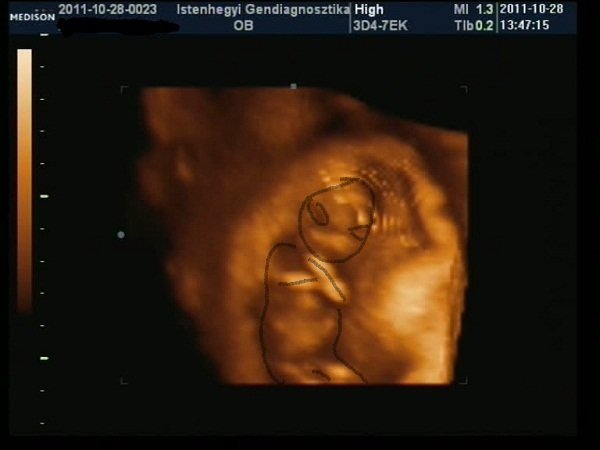

Nagyon jó volt az Istenhegyin, pikk-pakk levették a vért, aztán nem egészen egy óra múlva megvolt az uh, rettenetesen alapos volt a doki, 6-szor is megmérte a tarkóredőt (mert a határ határán volt, 2.4, és 2.5 felett szokott rezegni a léc, 3 felett rossz), aztán jól megnéztük mindenét, még 4D-ben is (sose voltam ilyenen:D), mindent elmagyarázott, végül kaptam egy dvd-t, és jó véreredményt kívánt.

– Akkor merek tippelni, mert nem fog haragudni, ha mégis tévedek. Szerintem kisfiú, és az ott egy kuki

Hoztam néhány képet a kukiról és az x-faktorról (utóbbit megoldókulccsal:D), valamint a "nagyokról", ahogy birtokba veszik a kanapét, és a lehető legszínesebben próbálják funkcióra bírni, valamint az Angelina Jolie Klub-ról, amit különböző balesetekben szerzett sebesüléseik miatt nyitottam…